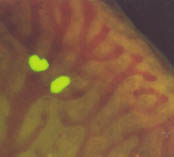

Cancer cells (green) trapped in capillaries. Chambers